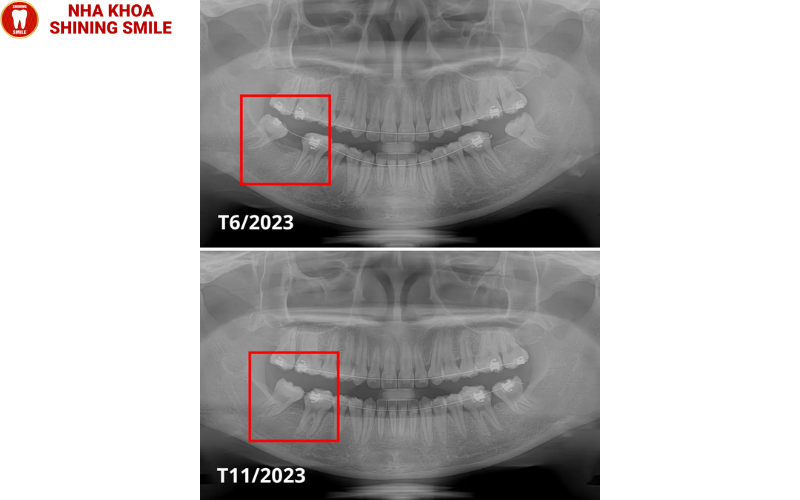

Trước và sau khi kéo răng số 7 thay răng số 6 tại Nha khoa Shining Smile